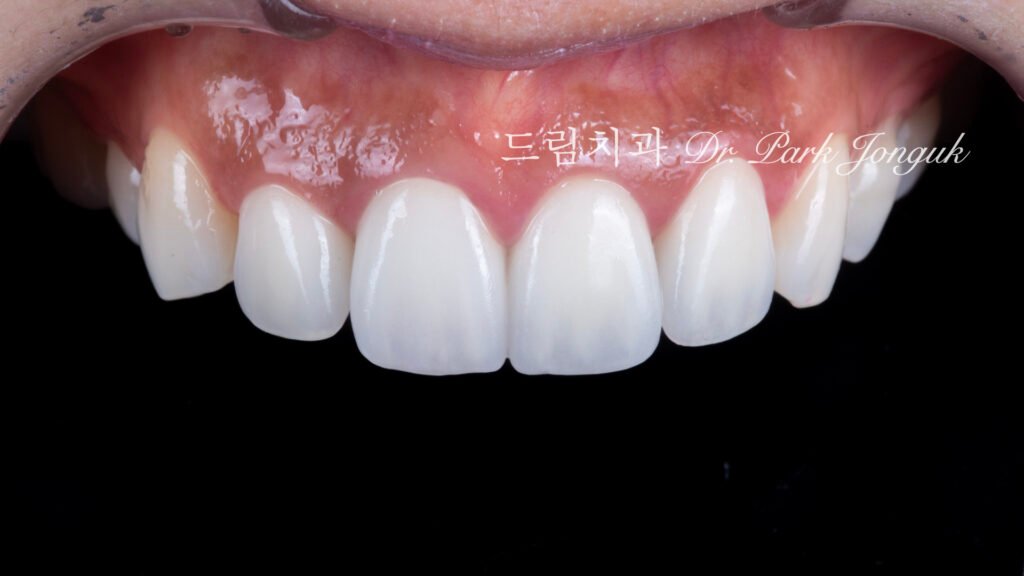

최종 결과: 4년 추적 관찰의 성공

사진 4, 5, 6은 치료 후 4년이 경과한 상태입니다. 놀라운 장기 안정성을 보여줍니다.

투명감과 자연스러움

투명감이 살아 있으면서도 자연스럽고 밝은 치아가 되었습니다.

절단연 투명감(Incisal translucency): 치아 끝의 투명감이 아름답게 표현되어 빛이 부드럽게 투과하고 산란(Light scattering)됩니다.

젊고 건강한 인상: 투명감은 젊고 건강한 치아의 특징으로, 노화되거나 병적인 치아는 불투명합니다.

색상 회복

밝고 생동감 있는 색상: 푸르스름하고 회색이던 색조가 밝고 생동감 있는 색으로 완전히 변했습니다.

자연스러운 다색성(Polychromaticity): 단순히 하얗기만 한 것이 아니라, 자연스러운 색상 그라디언트(Color gradient)와 깊이감(Depth)이 있어 진짜 치아처럼 보입니다.

우아한 형태

입체적 특성화(Three-dimensional characterization): 획일적이지 않고 각 치아가 발육엽(Developmental lobe), 표면 굴곡, 미세 텍스처를 갖습니다.

자연스러운 불완전성(Natural imperfection): 완벽한 대칭이나 매끄러움이 아닌, 자연치아의 미묘한 불규칙성이 재현되었습니다.

4년 장기 안정성

가장 중요한 발견은 4년이 경과했는데도 여전히 완벽하다는 것입니다.

색상 안정성(Color stability): 변색이나 색조 변화 없이 초기 색상을 유지합니다.

구조적 완전성(Structural integrity): 파절, 균열, 탈락(Debonding) 없이 완벽한 상태입니다.

치은 건강(Gingival health): 잇몸 염증, 퇴축, 변색 없이 우수한 치은 건강을 보입니다.

이는 제대로 된 재시술의 장기 성공률을 입증합니다.